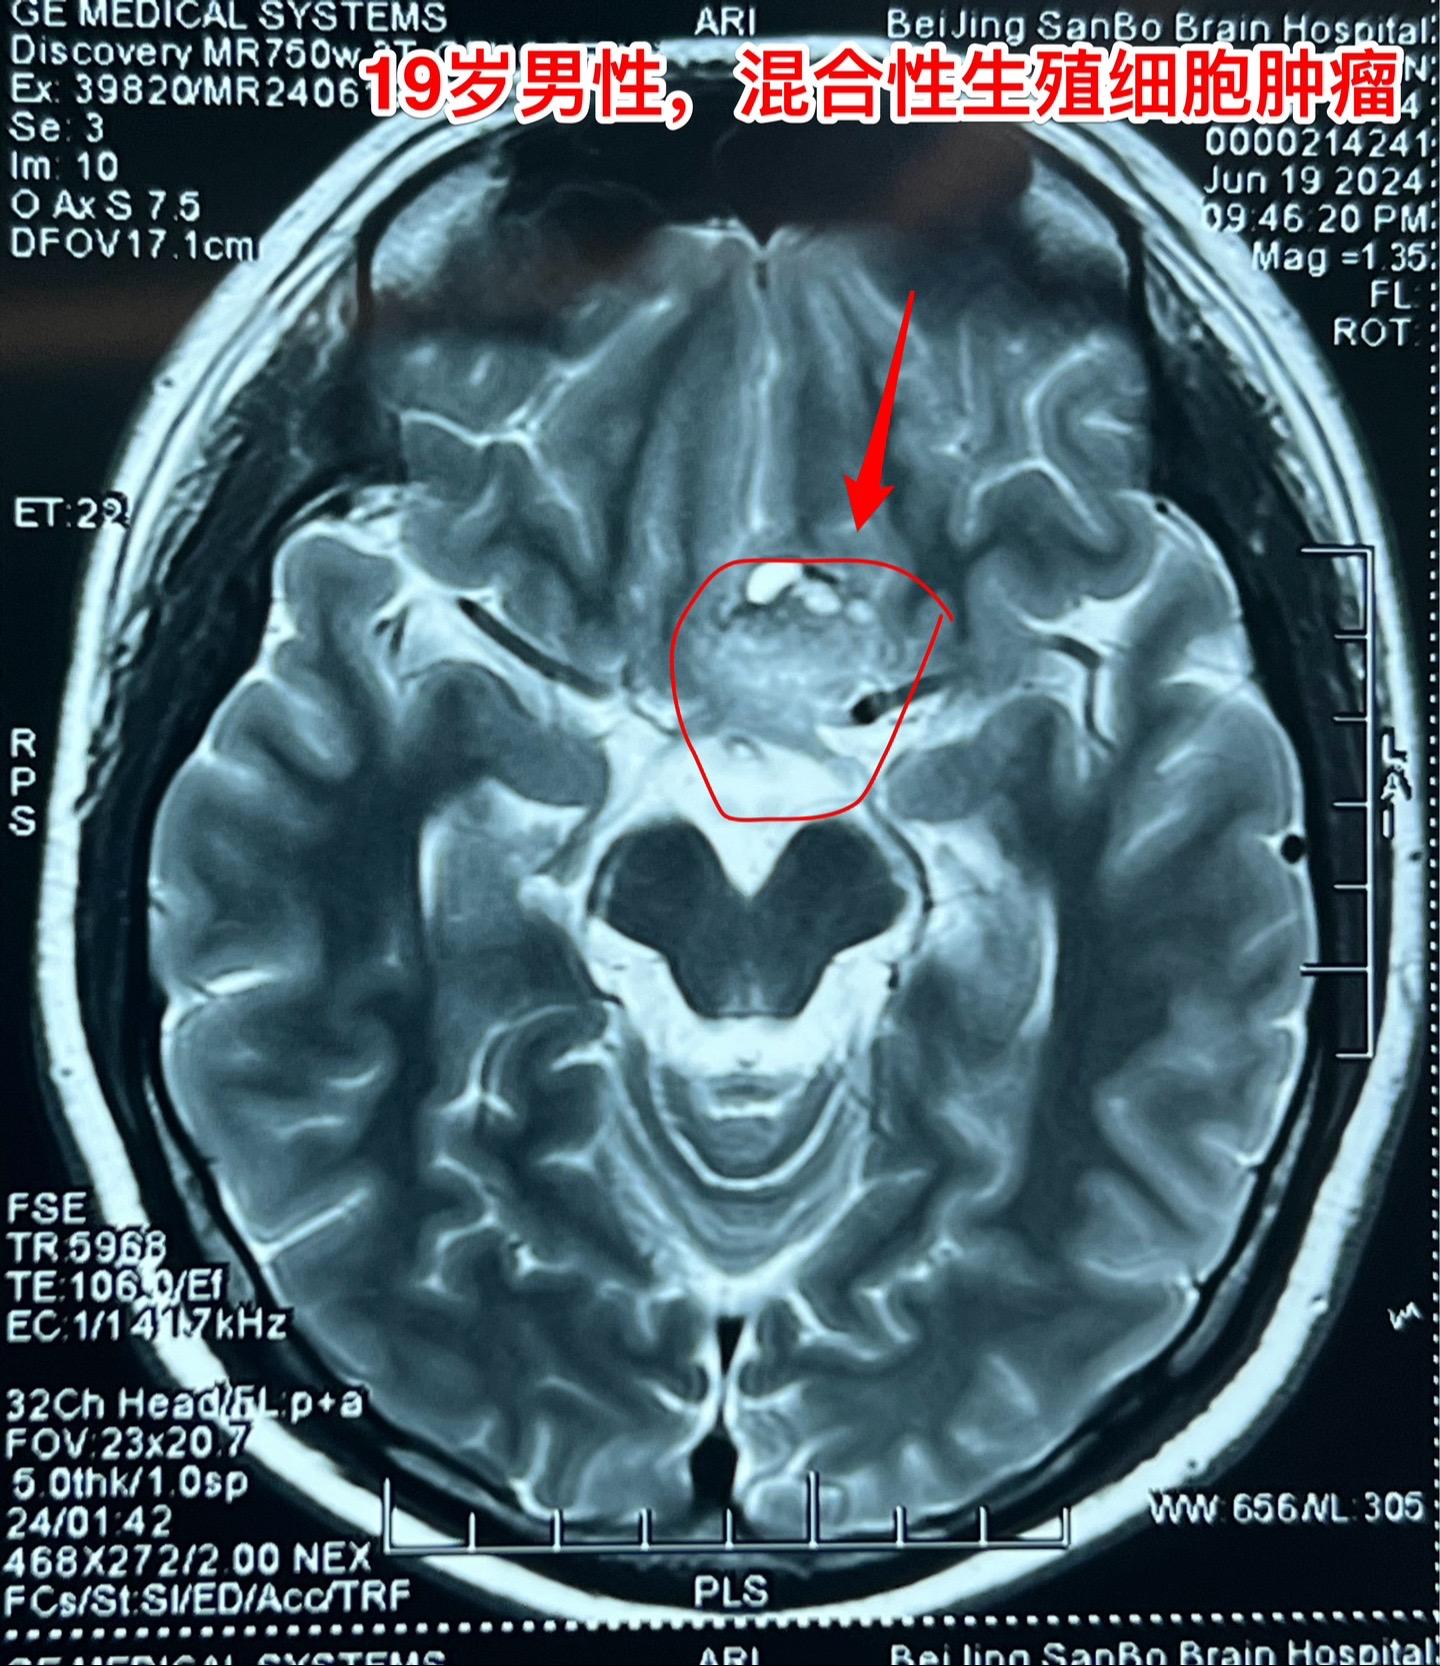

混合性生殖细胞肿瘤复发需要综合治疗。19岁莆田籍男性,三年半前还是新冠疫情期间,就因头痛发现松果体区肿瘤,怀疑是生殖细胞肿瘤,经过伽马刀治疗+化疗,肿瘤消失了,病人能正常上学。 2023年12月病人出现左眼视力下降,多饮多尿症状,复查磁共振显示鞍区肿瘤。取肿瘤活检提示是混合性生殖细胞肿瘤。化疗两个疗程,肿瘤体积稍微变小,停止化疗后肿瘤体积有增大,左眼视力呈恶化趋势,到北京三博来就医时左眼已经失明了。肿瘤的影像学资料见图。化验肿瘤标记物AFP、beta HCG均高于正常,这种情况下首选的是作